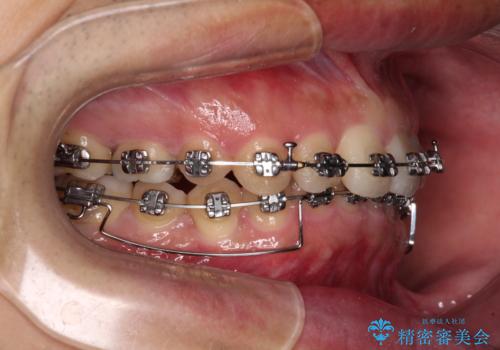

ディープバイトの方は項合力が強大であることが特徴のため、仕上がりを重要視して、ワイヤー装置にて矯正治療を行うこととしました。

右上と左下は永久歯が欠如しており、大きさの大きく異なる乳歯が残存していたため、奥歯の咬み合わせを構築するために苦労しました。

元々隙間の空いていた上顎の正中は、後戻りのリスクが高いため、下顎前歯同様ワイヤー固定を行いました。